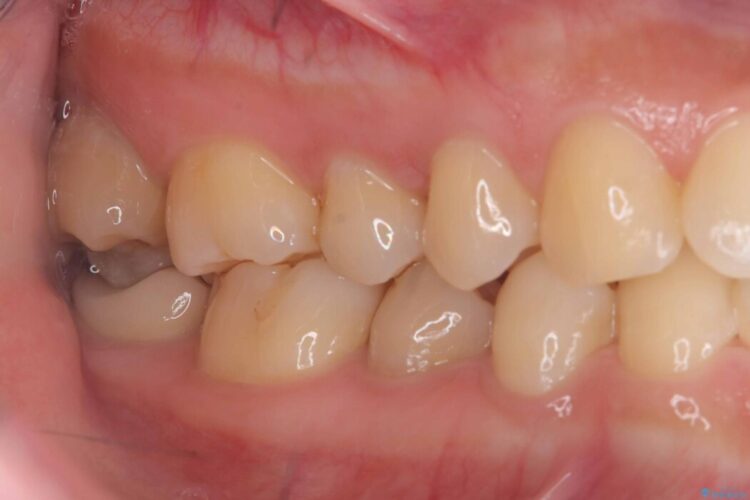

歯と歯の間に虫歯があった患者様です。

噛む面や外側にも過去の詰め物が入っている状態で、このように詰め物の範囲が大きいと治療後に歯が割れてしまうリスクが高くなります。